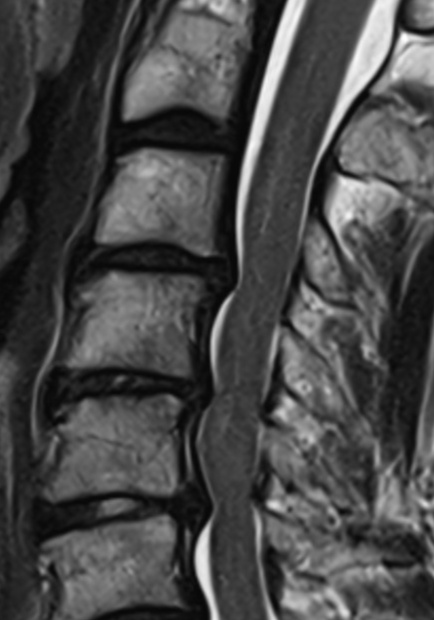

Zervikale Spinalkanalstenose MRT

Abbildung einer zervikalen Spinalkanalstenose im Segment HWK5/6 in einer sagittalen T2 MRT Sequenz.